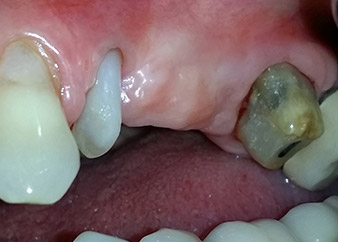

Una paziente donna di 58 anni lamentava dolore e aumentata mobilità del dente di appoggio del ponte 24. Era presente infiammazione periodontale con tasche di profondità di 7 mm a livello mesiobuccale e di più di 12 mm a livello distale, nonché coinvolgimento di terzo grado della forcazione. Inoltre, la radiografia rivelava una lesione periodontale estensiva attorno alla regione apicale del dente pretrattato 24 (in altro luogo) a livello endodontico (Fig. 1).

Un anno più tardi, sono stati estratti i denti 25 e 26 in seguito a trauma e per motivi endoperiodontali, prima del posizionamento del ponte. Era stata diagnosticata una lesione endoperiodontale combinata in corrispondenza del dente 24, di eziologia incerta. La paziente desiderava conservare i denti 24 e 27 di appoggio al ponte e non accettava una protesi rimovibile finale, o temporanea. Si è pertanto deciso di fare il possibile per conservare entrambi i denti, nonostante la prognosi negativa basata sugli esiti clinici e radiologici.